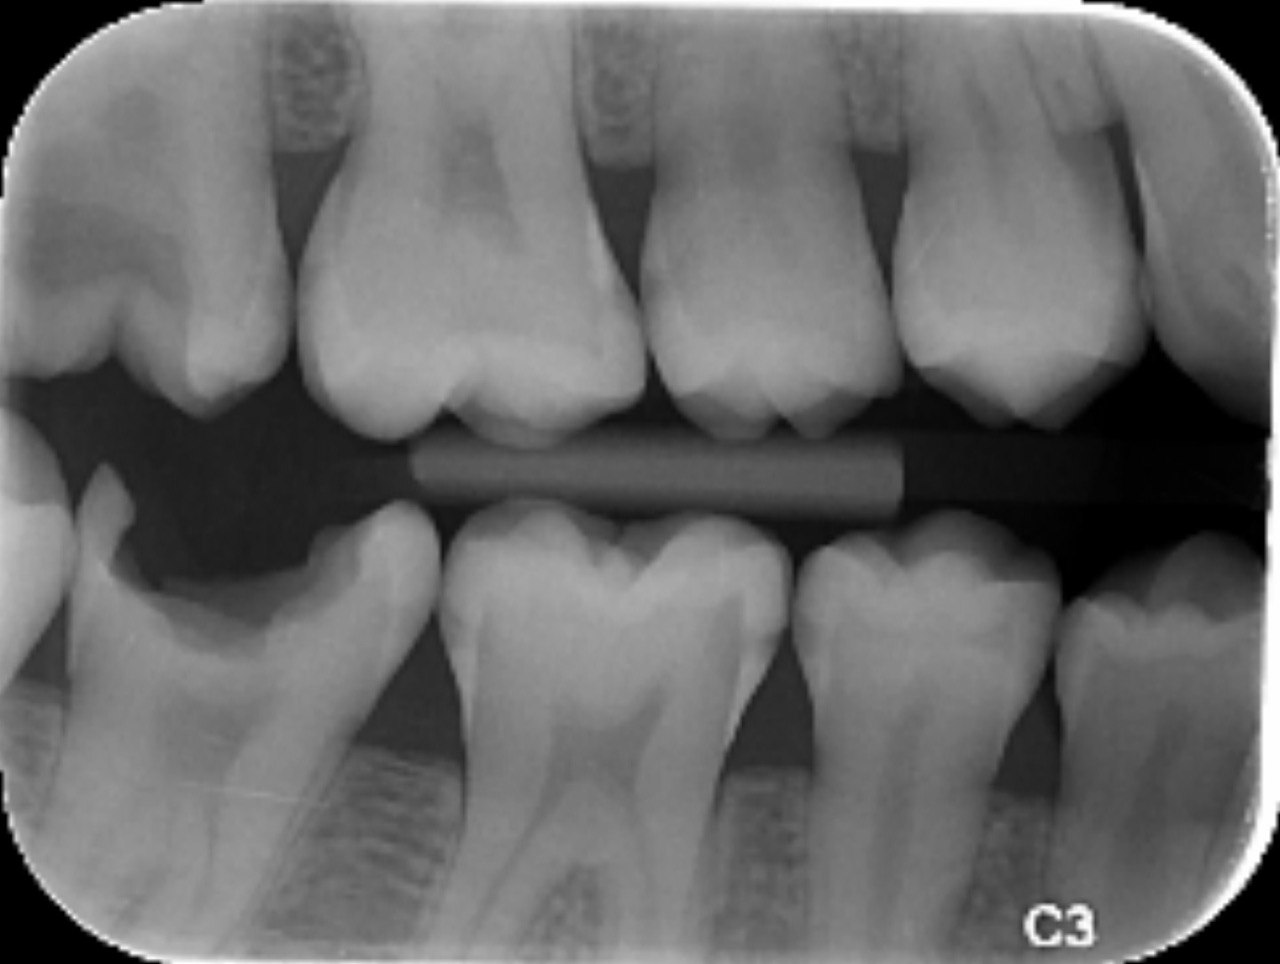

18. Which surfaces need restoration?

22. What is the caries level of distal surface of tooth # 3.3?

23. What is the caries on distal surface of the tooth #2.4?

24. What are the caries level in distal surface th # 4.4, Mesial surface tooth # 4.5 respectively?

25. What are the caries level in distal surface of the tooth # 1.4, Mesial surface of the tooth # 1.5 respectively?

26. What are the caries on distal surface of the tooth # 4.6 and mesial surface of the tooth # 4.7?

27.  what is the condition of the distal surface of the tooth # 4.5?

28. What are the coditions in the distal surface of the tooth # 4.5 and mesial surface f the tooth # 4.7 respectively?

29. What is the condition of the distal surface of the tooth # 4.7?

30. What are the conditions in the distal root surface of the tooth # 3.7 and distal root surface of the tooth # 3.8 respectively?

31. What is the condition of the occlusal of the tooth surface of the tooth # 4.7?

33. What is the caries level of the distal surface of the tooth # 1.6?

34. What is the proper tretment for mesial surface of the tooth # 1.6?

35. What is the condition of the distal surface of the tooth # 4.7?

41. Which surface shows root caries?

44. What is the caries level of mesial of the toth # 1.6?

48. Which surface does not show caries?

49. Which surface needs restoration?